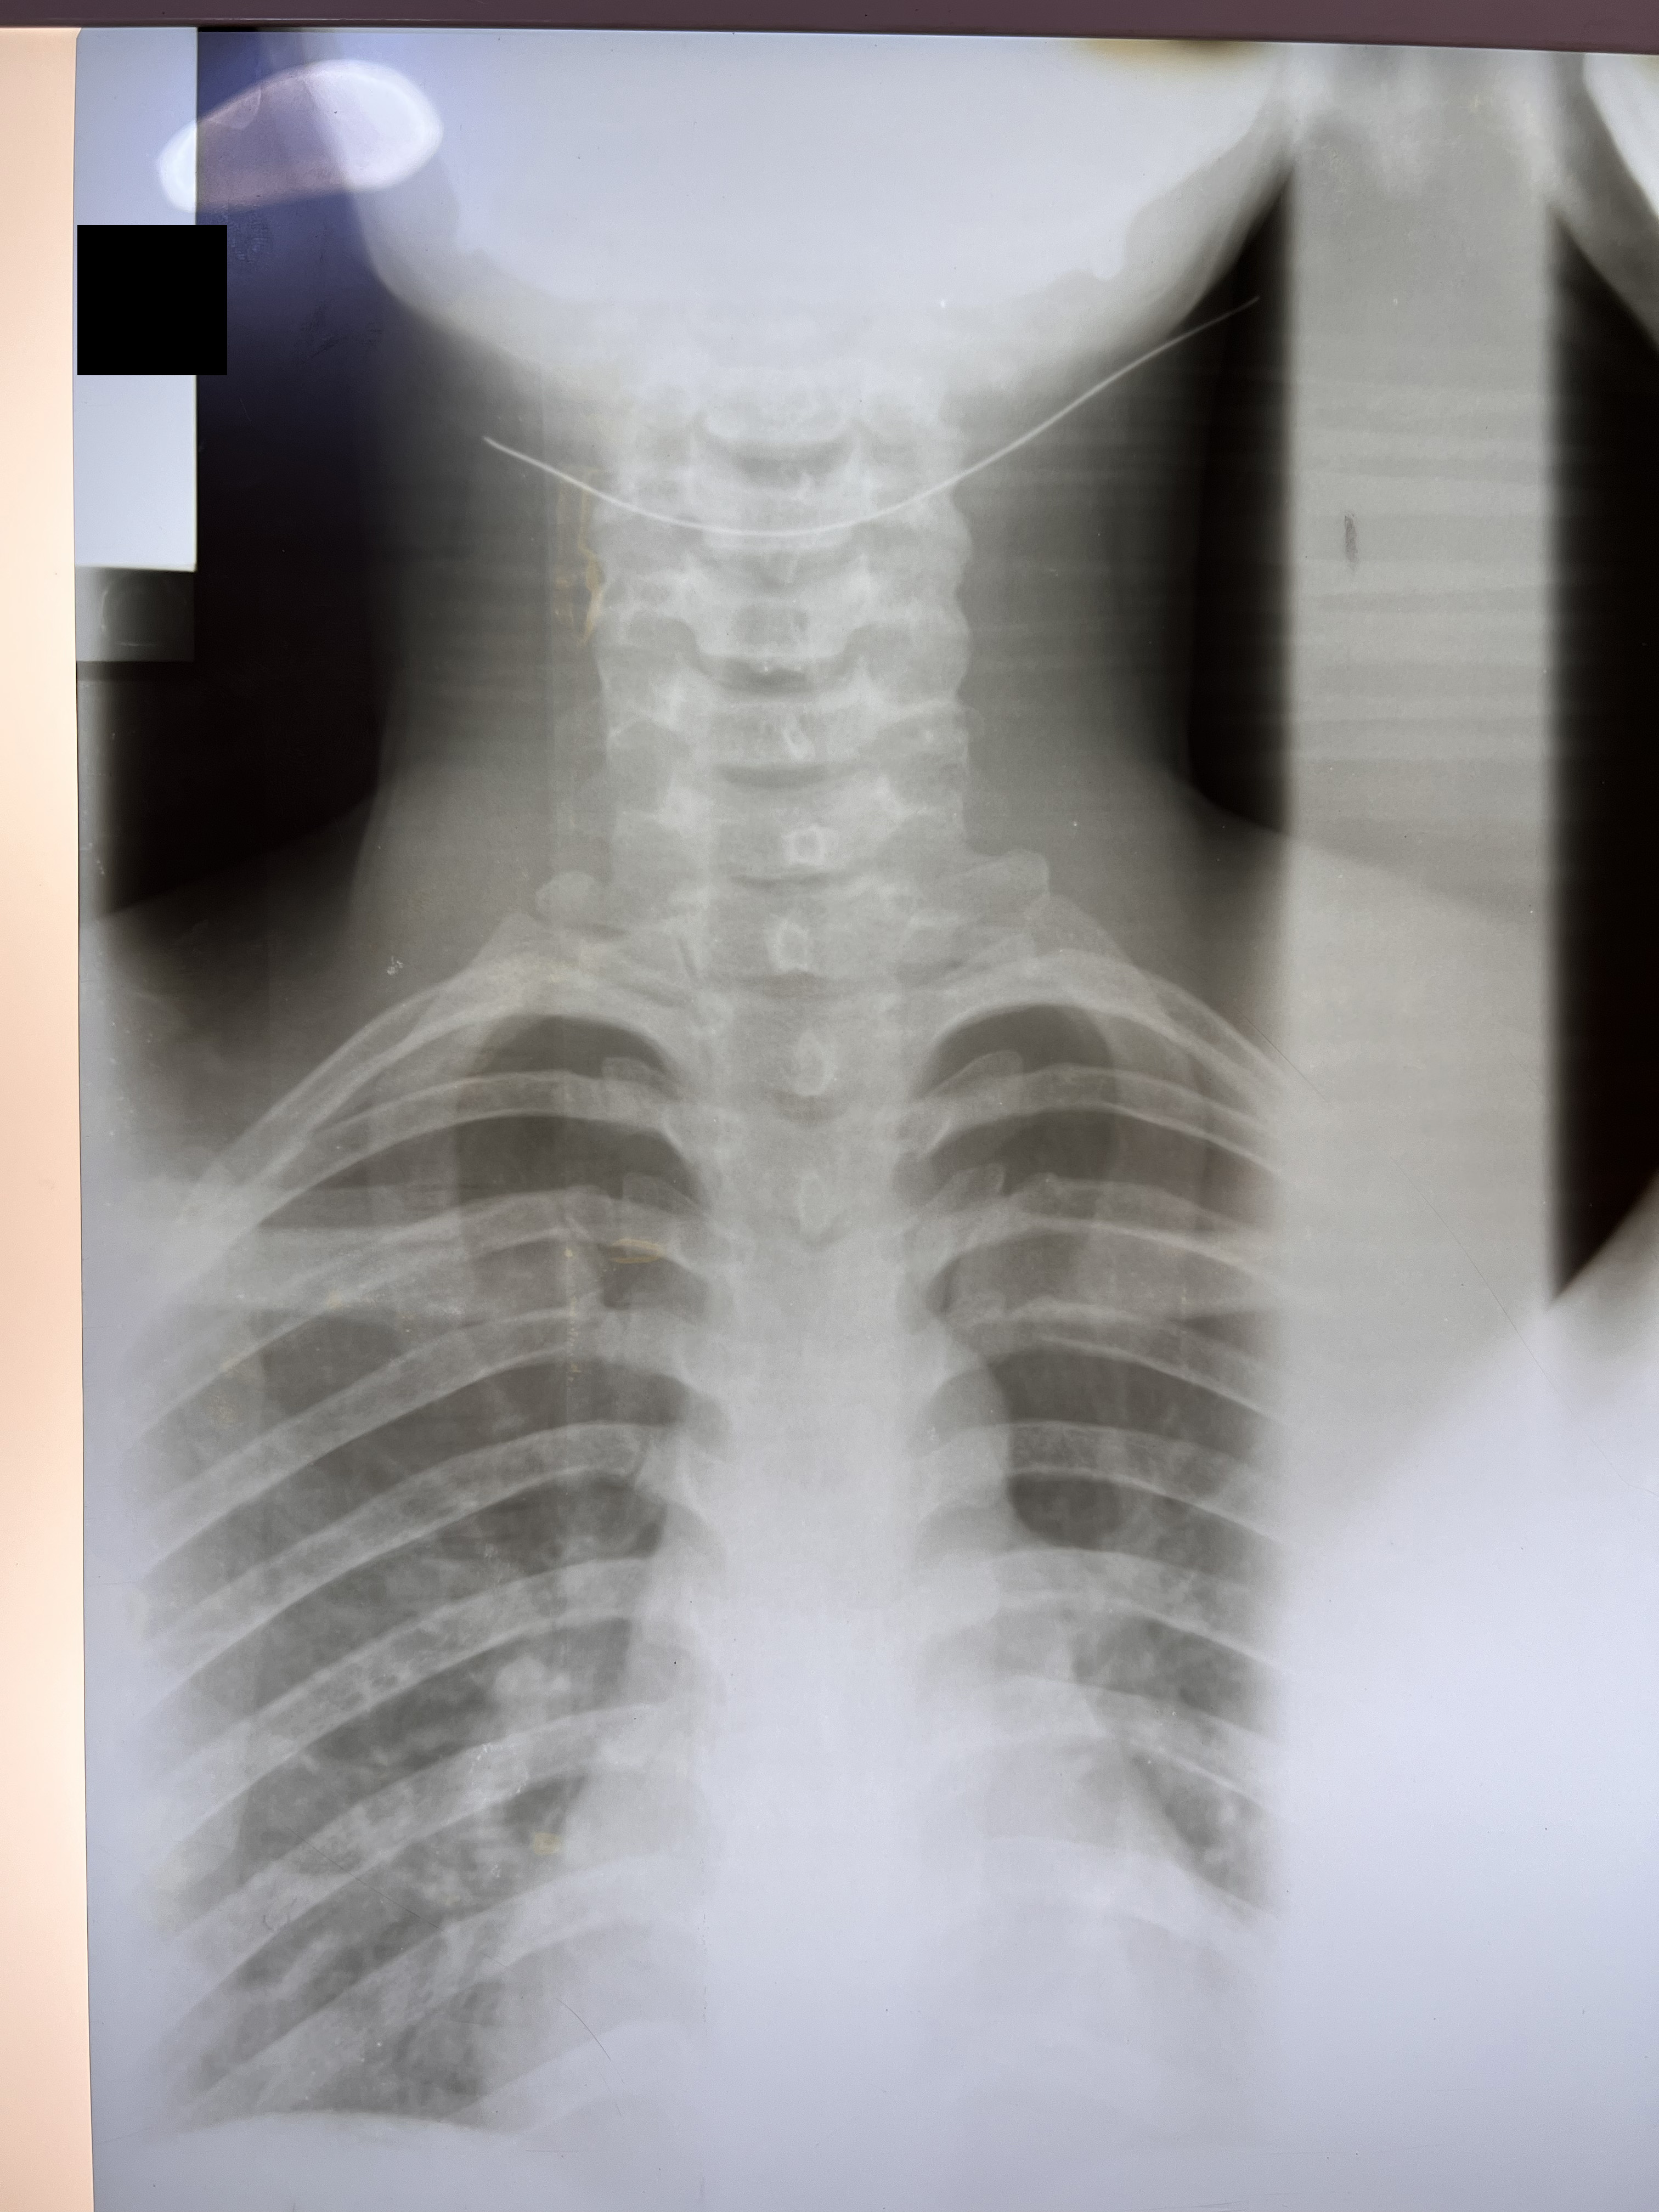

Chiropractic X-Rays

In partnership with Nova Wellness Centre led by Dr Asheley Ashietey in Accra, we conducted chiropractic examinations of 100 women working as kayayei in Kantamanto Market ranging in ages from 15 to 44, with varied experience carrying in the market from those who had been working for a few weeks to some women who had carried bales for 20 years. Nearly every study participant reported significant pain as a result of headcarrying and x-rays indicated spinal deterioration and deformities beginning within months on the job. Such physiological impacts coupled with severely polluted, cramped and violent living conditions set the stage for catastrophic injury.